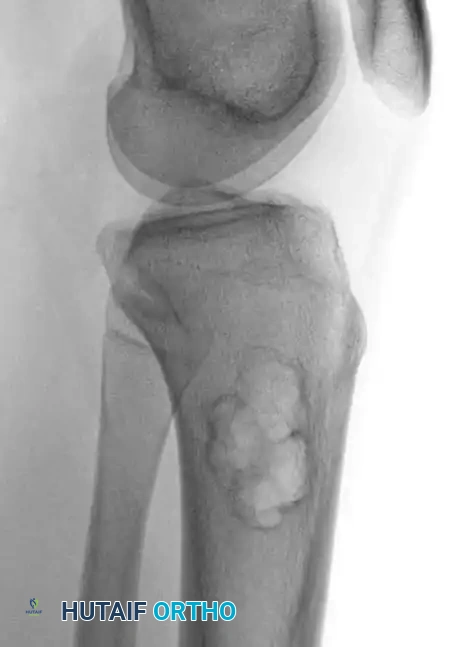

On plain radiography, an NOF presents as a well-defined, lobulated, and eccentrically located radiolucency within the metaphysis.

Fig. 20-8 A and B: Anteroposterior and lateral radiographs demonstrating a classic nonossifying fibroma of the proximal tibia in a 15-year-old patient. Note the eccentric location and sclerotic margins.

A multilocular appearance with distinct ridges in the bony wall, sclerotic scalloped borders, and focal erosion of the inner cortex are hallmark findings. Crucially, there is an absolute absence of periosteal reaction unless a pathological fracture has occurred.